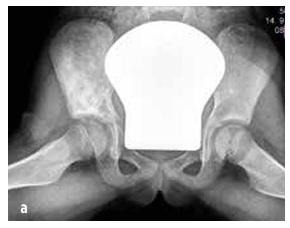

Ewingův sarkom postihující skelet pánve

Obrázek č. 7